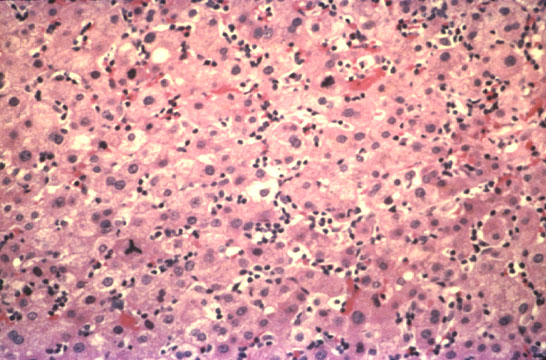

Fig. 133 - Infectious mononucleosis hepatitis

Marked mononuclear cell infiltration of the sinusoids without significant necrosis. H&E stain.

Fig. 134 - Infectious mononucleosis heapatitis

High power of previous illustration showing the signs of high regenerative activity: binucleate cells and a mitotic figure. H&E stain.